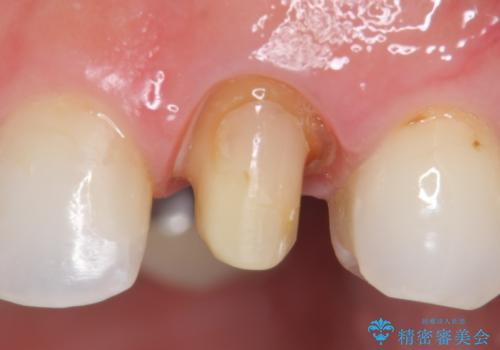

- 根管治療後歯が黄色くなってきたのでセラミックにしたいといらっしゃった方の症例です。

再根管治療後、オールセラミッククラウン(スペシャル)による補綴を行いました。

- オールセラミッククラウン(スペシャル)…¥130,000、仮歯…¥10,000、ファイバーコア…¥20,000費用は治療当時の料金となります